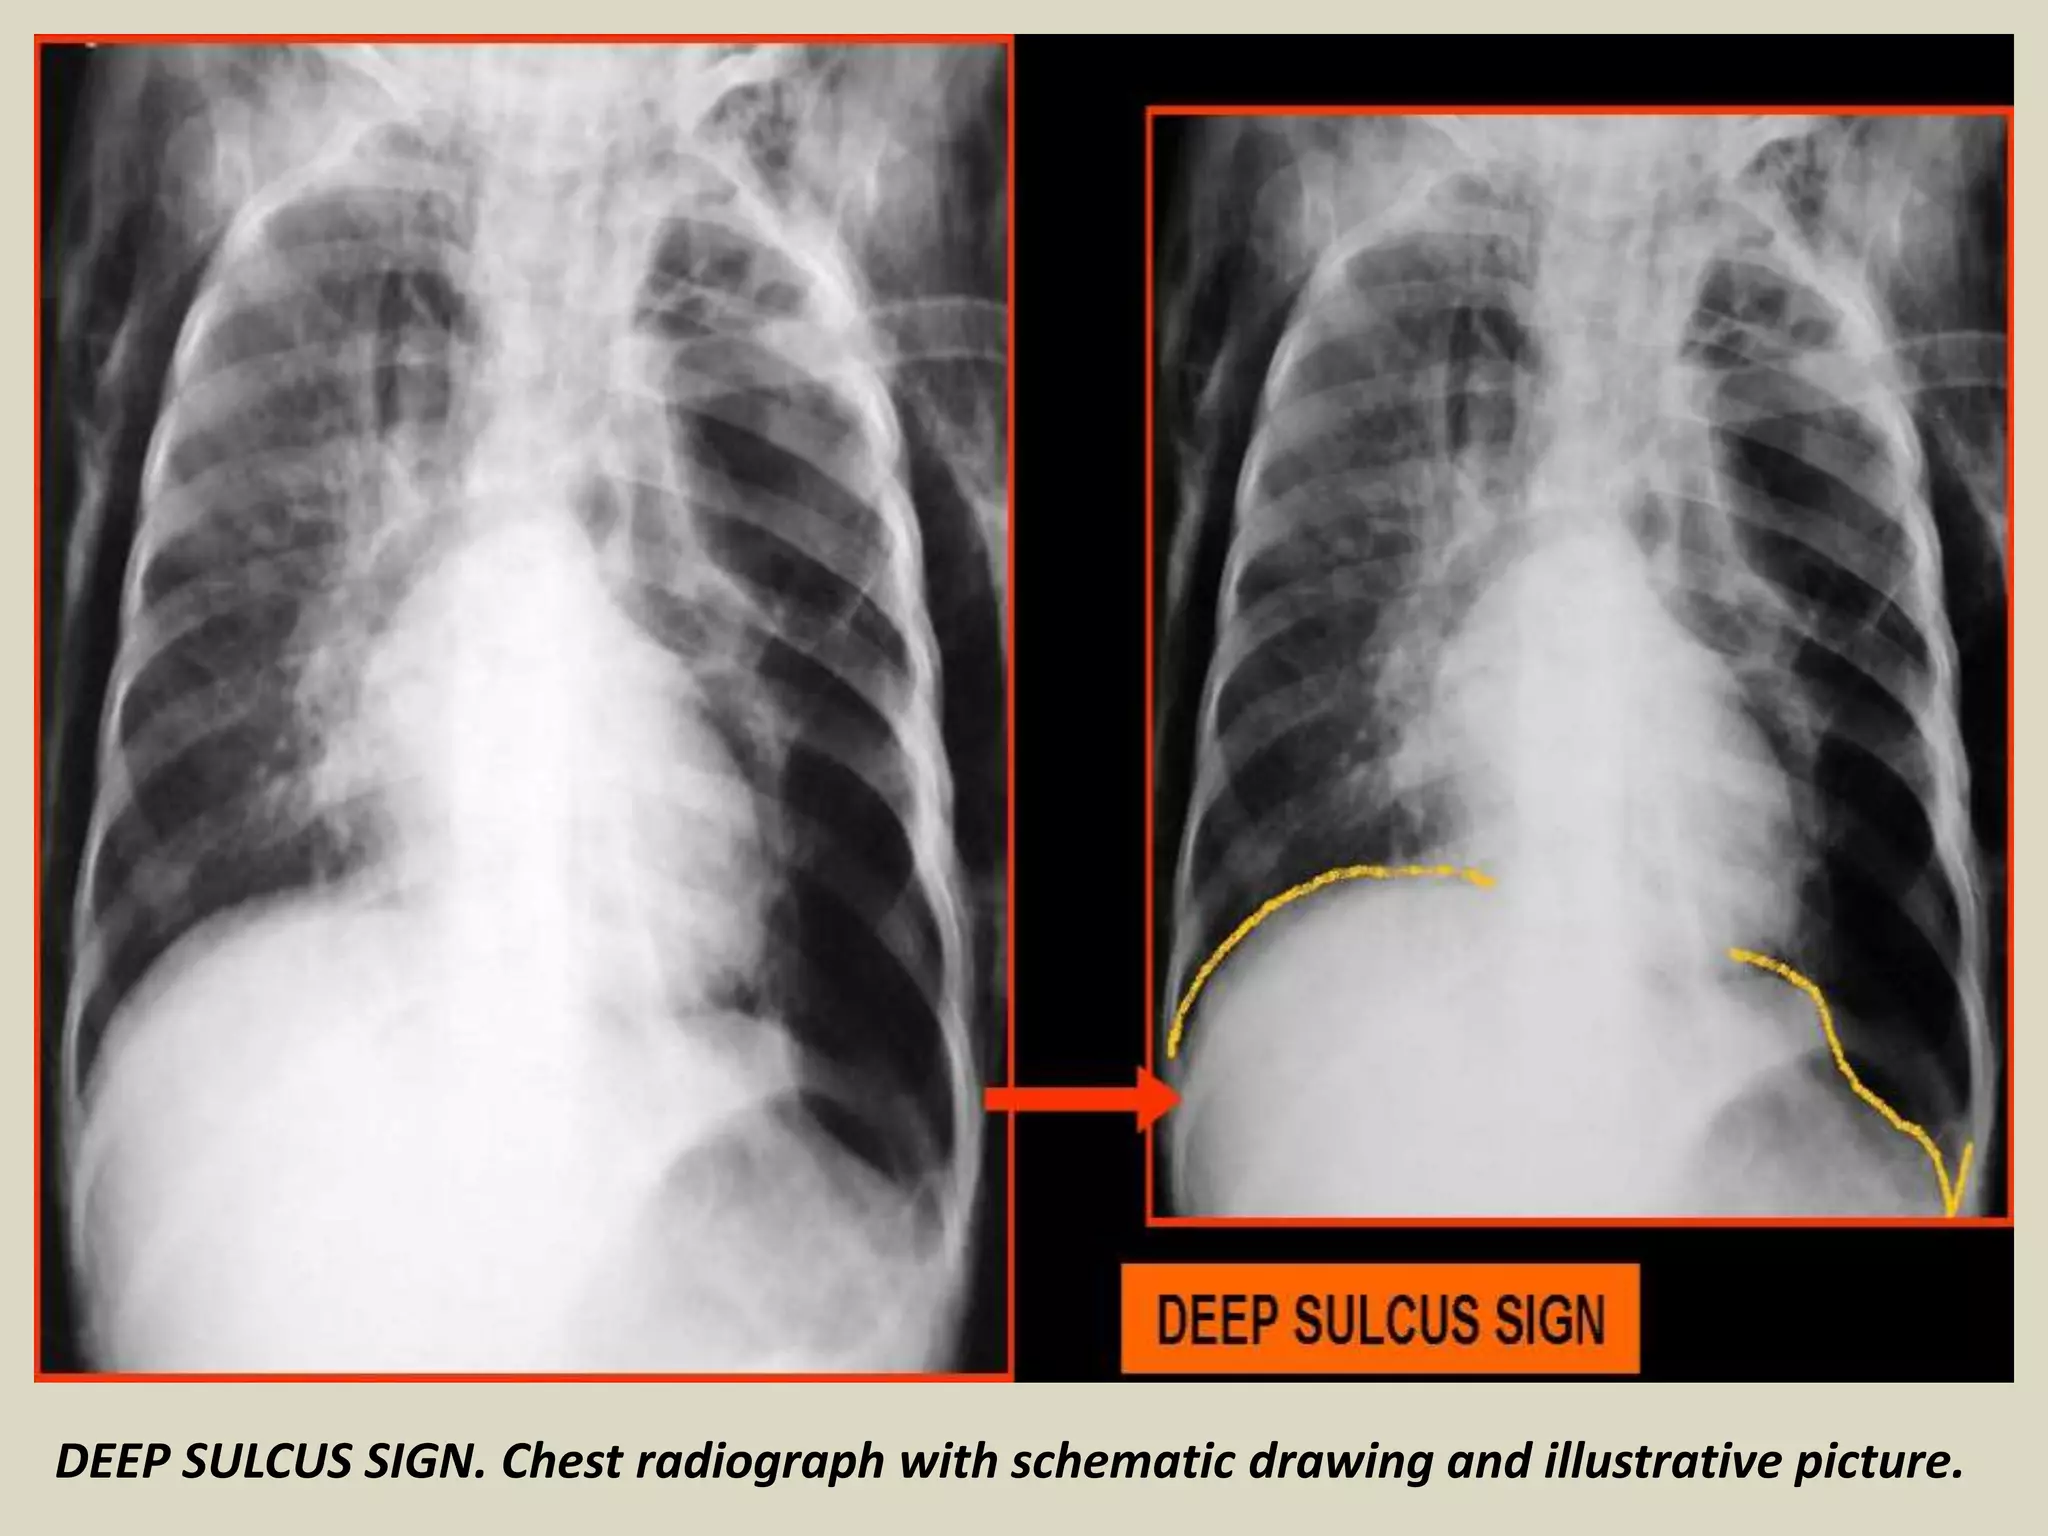

DEEP SULCUS SIGN

The presence of radiolucency in a deep costophrenic

sulcus on a supine thoracic radiograph is characteristic

of a pneumothorax in a supine patient

Seen on X-rays in supine position

Intrapleural air rises to the highest portion of the

hemithorax leading to the presence of a lucency in the

anteromedial, subpulmonic, and lateral basilar space

adjacent to the diaphragm

30% pneumothoraces are undetected

It is useful in confirming suspected pneumothorax on

AP supine radiography in compromised patients, such

as those in the intensive care setting

DEEP SULCUS SIGN. Chest radiograph with schematic drawing and illustrative picture.

• Seen on radiographs in supine position

• Characteristic of pneumothorax

• 30% pneumothoraces are undetected

• Lucency in lateral costophrenic angle

• Air collects anteriorly and basally

• Useful in neonates and ill patients

• Include lateral costophrenic angles

DEEP SULCUS SIGN Thepresence of radiolucency in a deep costophrenic sulcus on a supine thoracic radiograph is characteristic of a pneumothorax in a supine patient Seen on X-rays in supine position Intrapleural air rises to the highest portion of the hemithorax leading to the presence of a lucency in the anteromedial, subpulmonic, and lateral basilar space adjacent to the diaphragm 30% pneumothoraces are undetected It is useful in confirming suspected pneumothorax on AP supine radiography in compromised patients, such as those in the intensive care setting

DEEP SULCUS SIGN.Chest radiograph with schematic drawing and illustrative picture.